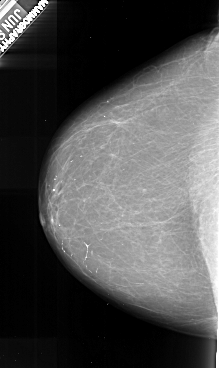

A_1010_1.LEFT_CC

LEFT_CC LINES 6256 PIXELS_PER_LINE 3721 BITS_PER_PIXEL 16 RESOLUTION 42 NON_OVERLAY